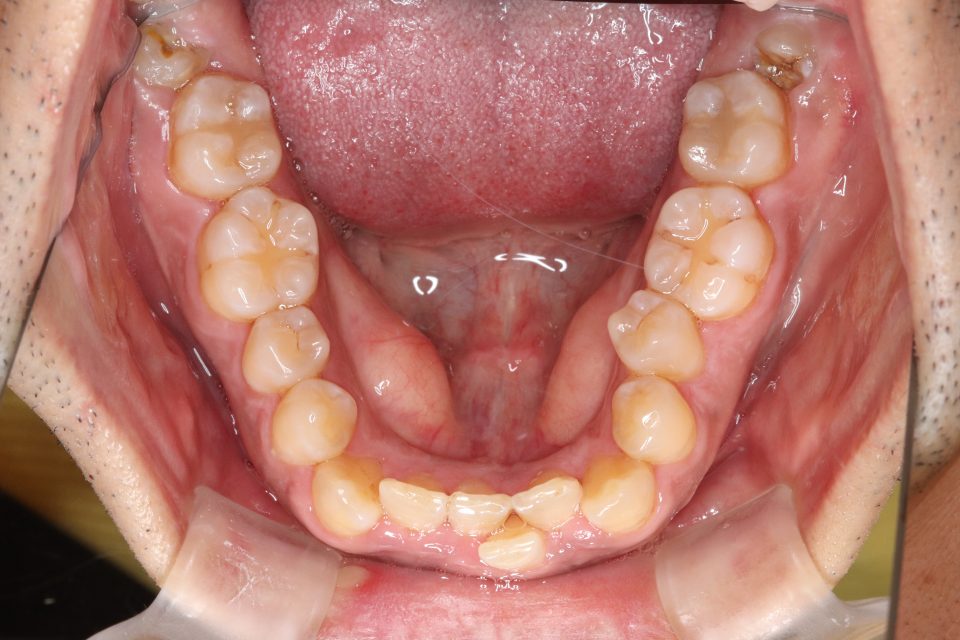

矯正治療前

30代男性です。

歯の凸凹が気になると来院されました。

目立たない装置・取り外し可能なマウスピースタイプでの矯正治療を

希望されてましたのでマウスピース型矯正装置(インビザライン)で矯正治療を行いました。

親知らずを3本抜歯して、歯のやすりがけ(IPR)を行っています。